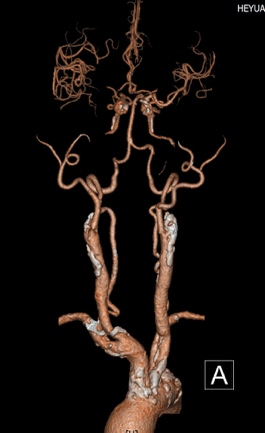

2月16日,72岁的黄先生在家中突发左侧肢体无力伴言语不清,家属将其送至我院急诊科就诊,卒中团队会诊后考虑急性脑卒中,NIHSS评分:20分,并立即护送患者至放射科。放射科医技护启动绿色通道,在3分钟内完成一站式卒中CT检查,并对脑CT灌注(CTP)及CT血管造影(CTA)图像进行快速评估:可见患者双侧颈内动脉及右侧大脑中动脉均闭塞(图1);CTP显示患者右侧大脑半球血流灌注减低(图2),但存在较大面积的缺血半暗带(图3),这提示如果能及时改善血运,可挽救大部分缺血脑组织,显著缩小脑梗死的范围,进而改善患者预后。基于可靠的影像证据,神经内科卒中团队当机立断通过急诊介入手术成功取栓并扩张颈内动脉,患者右侧大脑半球及时恢复了血供。术后第2天患者四肢、言语功能恢复良好,NIHSS评分:7分。术后第3天后MRI复查显示脑梗死范围远远小于术前低灌注区域(图4)。

图1:CTA示双侧颈内动脉及右侧大脑中动脉闭塞